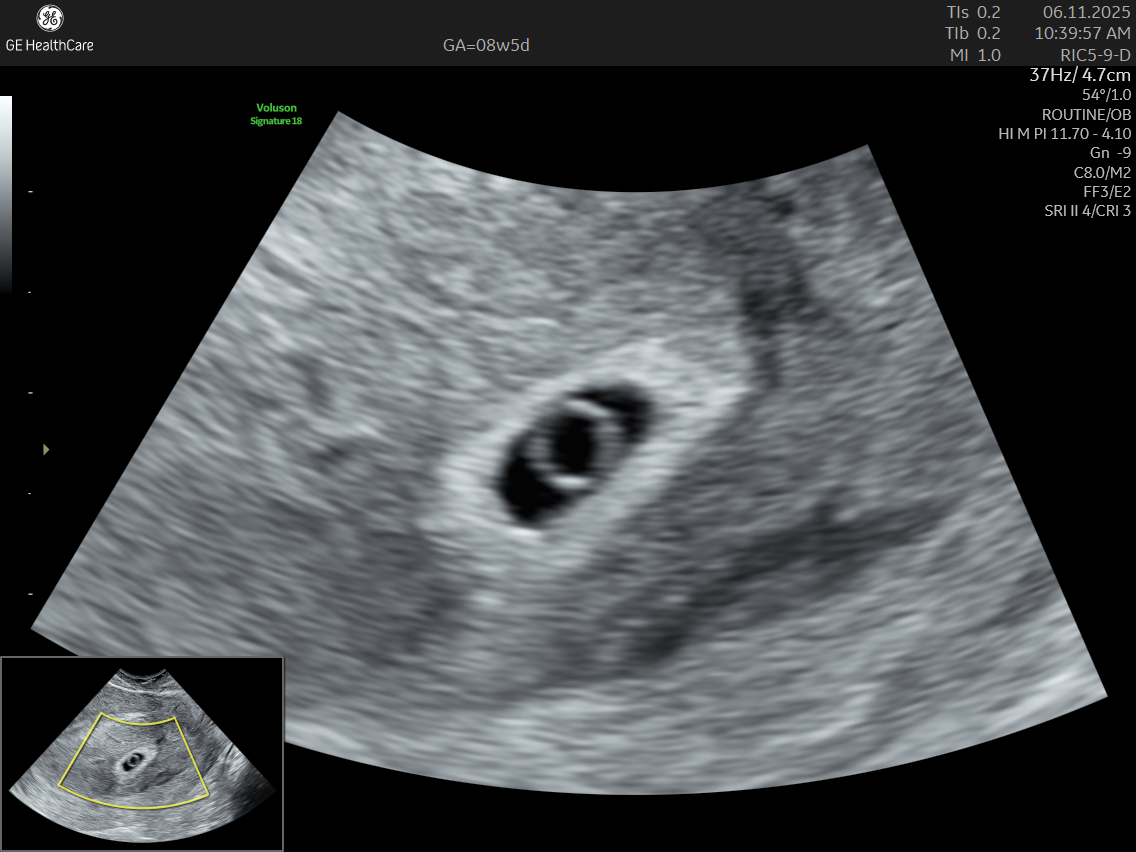

A Dating and Viability Scan is the first critical ultrasound in your pregnancy journey. Performed between 6 – 8 weeks, it confirms your pregnancy’s health, establishes how far along you are, and ensures an accurate start to your prenatal care.

- Usually conducted transvaginally for clear imaging

What Can The Scan Detect?